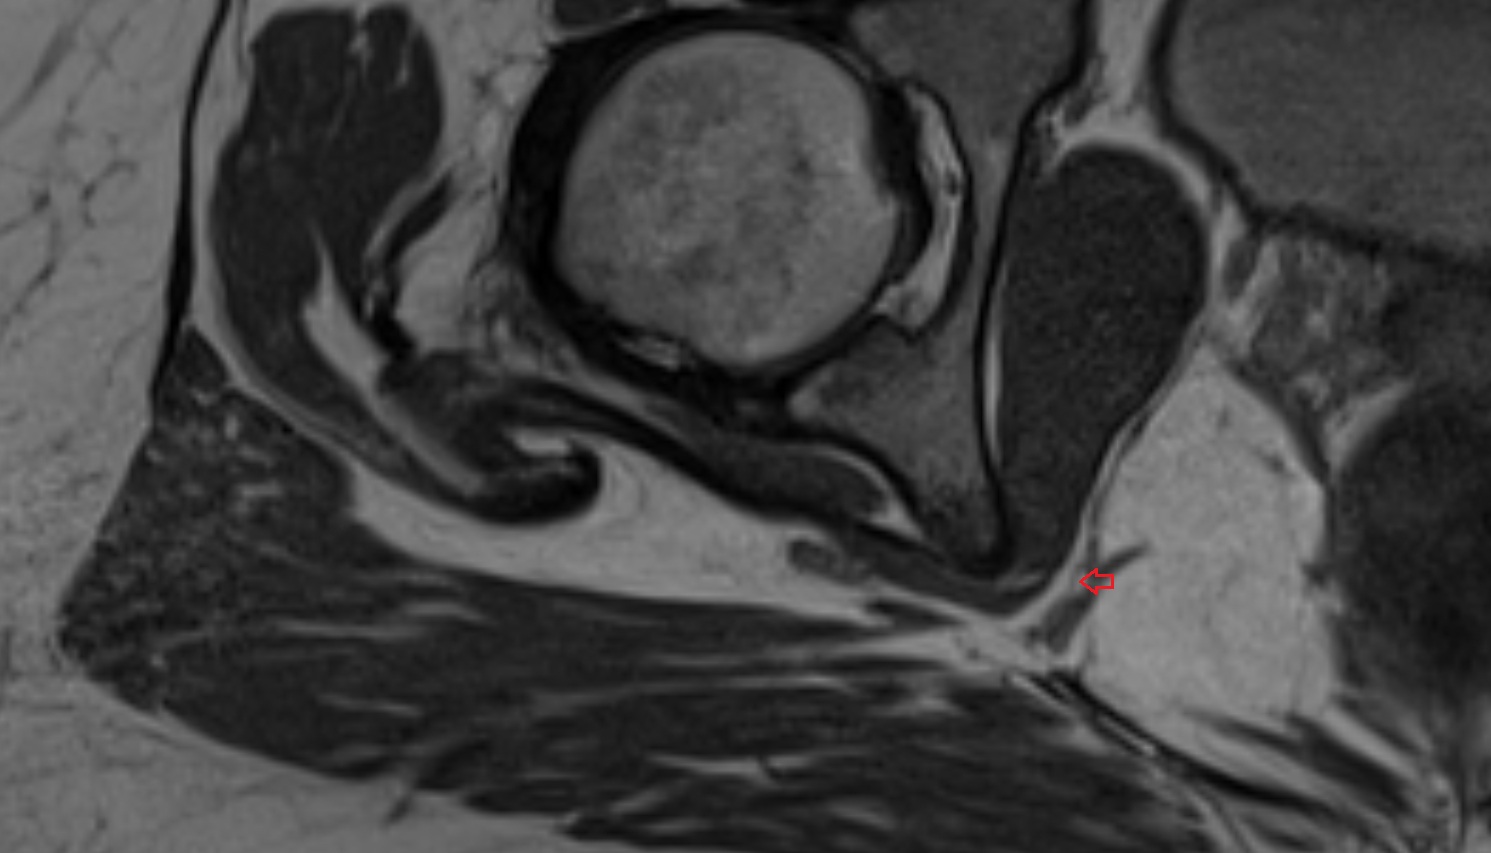

- Acetabular labrum

- Articular capsule of hip joint

- Hip joint